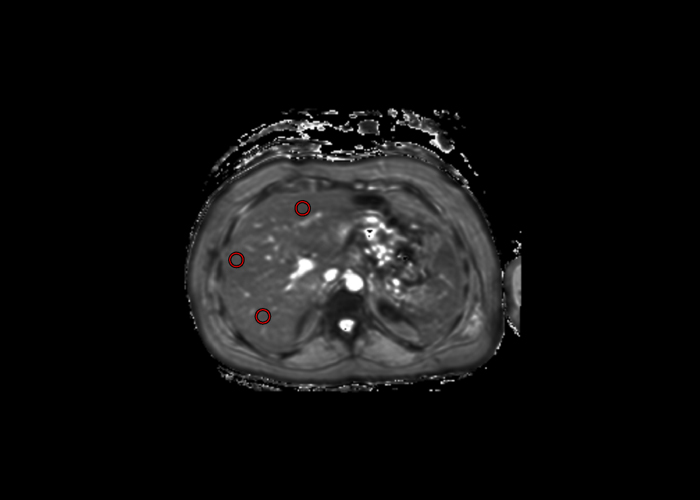

A través de mapas t2* medimos y cuantificamos el hierro en el hígado.